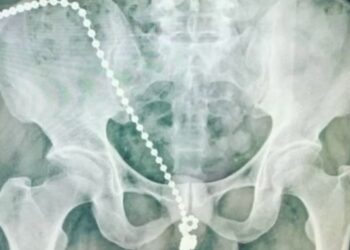

O caso bizarro foi registrado em um hospital de Taiwan. O homem de 30 anos foi parar na mesa de cirurgia com dores agudas ap\u00f3s introduzir uma corrente de bolinhas de metal na uretra, com o objetivo de aumentar o prazer na hora da masturba\u00e7\u00e3o.<\/p>\n\n\n\n

Ele passou por cirurgia bem-sucedida e contou que n\u00e3o conseguiu retirar o aparelho por receio de machucar-se mais ainda. <\/p>\n\n\n\n

Segundo o urologista que o atendeu, foi preciso abrir o p\u00eanis do paciente e desatar o n\u00f3 que se formou na corrente. Depois foi reconstruido a ureta. <\/p>\n\n\n\n

Imagem: Reprodu\u00e7\u00e3o\/Universidade M\u00e9dica de Taipei<\/p>\n","post_title":"Prazer doloroso: homem passa por cirurgia ap\u00f3s introduzir corrente de bolinhas no p\u00eanis","post_excerpt":"","post_status":"publish","comment_status":"open","ping_status":"open","post_password":"","post_name":"prazer-doloroso-homem-passa-por-cirurgia-apos-introduzir-corrente-de-bolinhas-no-penis","to_ping":"","pinged":"","post_modified":"2022-06-28 19:20:21","post_modified_gmt":"2022-06-28 23:20:21","post_content_filtered":"","post_parent":0,"guid":"https:\/\/estadodoamazonas.com\/?p=35401","menu_order":0,"post_type":"post","post_mime_type":"","comment_count":"0","filter":"raw"},{"ID":34851,"post_author":"2","post_date":"2022-06-22 17:09:17","post_date_gmt":"2022-06-22 21:09:17","post_content":"\n